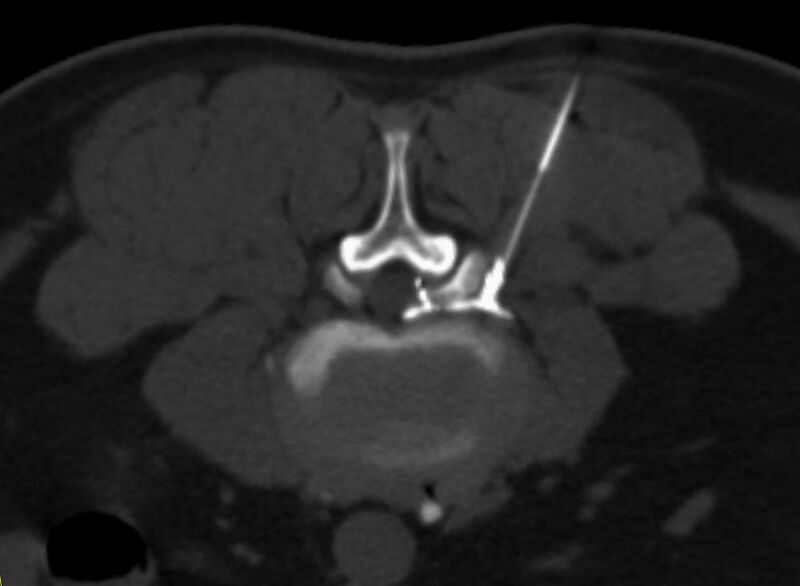

Interventionelle Eingriffe

Durchführung am Standort im Diakonissenkrankenhaus

• z. B. Punktionen zur Gewebsentnahme

Der Multislice-Scanner ermöglicht eine dem aktuellen Stand der Technik entsprechende, leitliniengerechte diagnostische Untersuchung sämtlicher Körperregionen. Darüber hinaus gestattet der neue Computertomograph auch eine für Arzt und Patient bequeme Durchführung CT-gestützter Interventionen wie z.B. Schmerztherapien der Wirbelsäule.